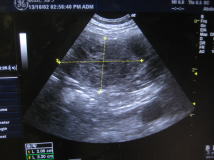

お腹の中をエコーで確認したところ、左の写真のように大きな黒い影が見つかり?停留睾丸?の可能性が高まりました。 |